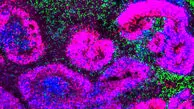

رکنا علمی: پژوهشگران با ارائه دقیقترین اطلسهای سلولی از مغز در حال توسعه انسان، موش و نخستیسانان غیرانسانی…